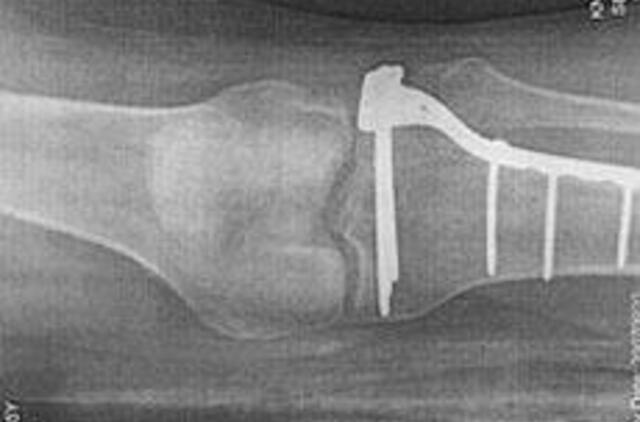

Osteoporozė – tai liga, kai sumažėja kaulų mineralų tankis ir jų kokybė. Tai silpnina skeleto kaulus ir didina kaulų lūžių riziką. Dažniausiai lūžta stuburo, riešo, šlaunikaulio, dubens, peties kaulai.